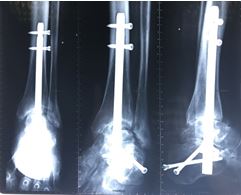

Переломы костей голени

В эту анатомическую область входят: переломы малоберцовой и большеберцовой костей. Они бывают как изолированными, так и комбинированными. Выделяют переломы проксимального и дистального отделов и диафизарные переломы.

В области дистального отдела костей голени следует отдельно выделить переломы наружной и внутренней лодыжек, как наиболее часто встречающиеся переломы. Повреждения в этой области приводят к выраженным функциональным нарушениям, так как гости голени выполняют опорную функцию.

Основным методом лечения этих повреждений является остеосинтез. В зависимости от локализации перелома возможно применение внутреннего остеосинтеза пластинами или интрамедуллярными штифтами.

Одними из первых малоинвазивные методики были разработаны и успешно применены при лечении пострадавших с диафизарными переломами большеберцовой кости. Фиксация отломков большеберцовой кости интрамедуллярным штифтом при локализации переломов в области диафиза – «золотой стандарт» успешно применяемый в ЦТиО.

Ключевым моментом данной операции является не только наличие минимальных по размеру хирургических доступов, но и возможность ранней нагрузки на оперированную ногу. Так интрамедуллярный остеосинтез позволяет вертикализировать пациента уже на вторые сутки после операции, либо значительно облегчает уход за пострадавшим, вынужденно находящимся в лежачем положении.

Также при переломах в данной области в ЦТиО с успехом применяется и накостный остеосинтез, который также представляет собой минимально-инвазивную методику. Во время проведения операции доступ осуществляется из маленьких разрезов, что не нарушает кровоснабжения кости. Это также позволяет сократить сроки восстановительного лечения.

Малоинвазивные методы лечения в умелых руках сотрудников ЦТиО ГВКГ им. Н.Н. Бурденко работают даже там, где, казалось бы, уже всевозможные варианты лечения исчерпаны. Например, при выполнении ортопедических операций по созданию артродеза голеностопного сустава, сросшихся в неправильном положении костей голени после перелома лодыжек.